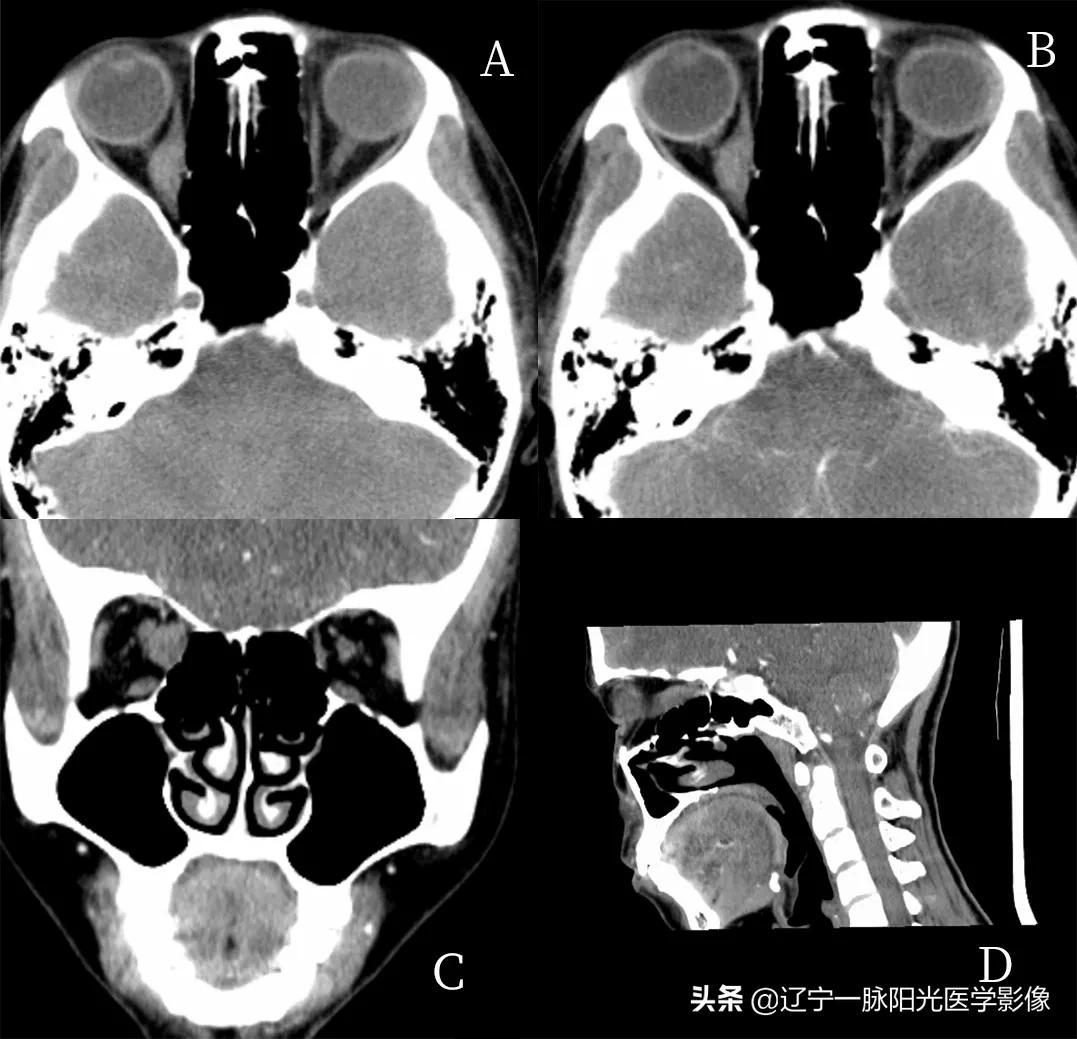

影像所见:

图 A、C 轴位及冠状位示右侧眼睑及球后软策划肿胀,脂肪间隙不清,见混杂稍低软策划密度影,增强扫描轻度强化

图 A、B、D 轴位、冠状位示右眼眶内球后肌椎内软策划填充,边界不清,密度不均,肌椎内病灶范围约为 4.1x3.2 cm,与眼环相比呈等密度,图 B、D 示增强扫描后病灶可见轻度强化

图 D 冠状位示右眼球受推外突,病灶包绕右侧视神经及眼肌,视神经及眼肌显示不清,肌肉间隙消失

影像诊断:右眼改变,考虑蜂窝策划炎伴眶内炎性假瘤形成